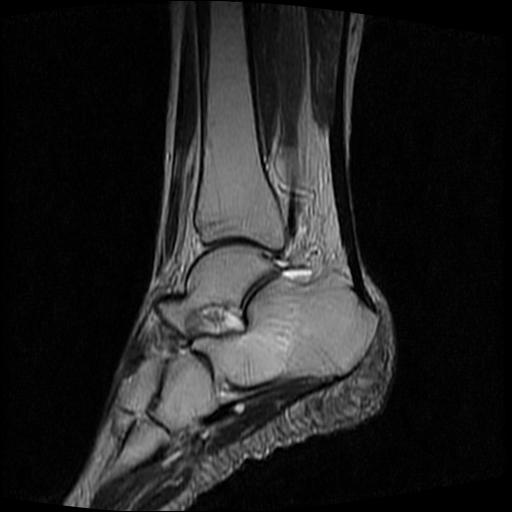

标题: MRI0968:女性,70岁,跟骨信号异常 [打印本页]

标题: MRI0968:女性,70岁,跟骨信号异常

女性,70岁,右侧跟骨疼痛2个月,负重时加剧,不负重时不疼。

胫骨下段,跟骨、距骨可见斑片状异常信号区;考虑:转移瘤

跟骨长t1长t2信号异常,边缘模糊(肿瘤一般边界清楚,故肿瘤不考虑),压脂像呈高信号--骨髓水肿(炎症?)。